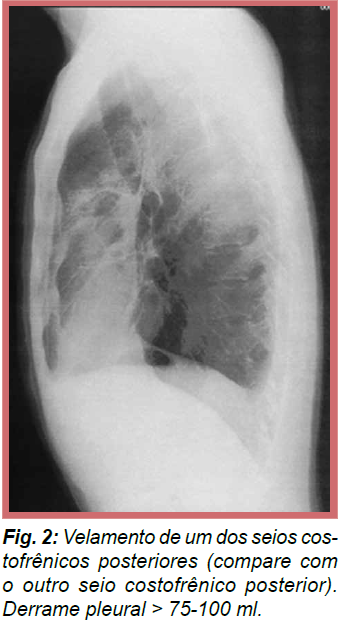

Qual das incidências do raio x de tórax é mais sensível para DP (entre PA e perfil)?

Perfil, pois é capaz de detectar DP através de velamento do seio costofrênico na presença de um menor volume de líquido (> 75-100), enquanto que em PA só se detecta > 175-200.

Imagem DP Perfil.

.